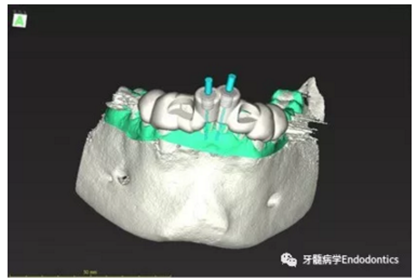

31、41叩痛明顯,牙冠變色(圖1)。溫度和牙髓電活力測(cè)試無反應(yīng)。兩張從不同角度拍攝的x線片顯示,相對(duì)于側(cè)切牙,雙側(cè)下中切牙都有嚴(yán)重的根管鈣化(圖2)。41有明顯根尖周暗影,31根尖周暗影不明顯。為進(jìn)一步證實(shí)31是否存在根尖周病變,同時(shí)精細(xì)觀察31、41的復(fù)雜結(jié)構(gòu),根據(jù)歐洲牙髓病學(xué)會(huì)CBCT應(yīng)用指南(2014),對(duì)患牙拍攝小視野、高分辨率CBCT。CBCT影像證實(shí)31、41均伴有根尖周炎和嚴(yán)重的根管鈣化(圖3)。距離根尖4mm可見根管影像。 由于患牙根管解剖結(jié)構(gòu)較為復(fù)雜,筆者決定使用特殊設(shè)計(jì)的微型鉆頭(直徑0.85mm)進(jìn)行“數(shù)字化導(dǎo)航牙髓治療”。 因此對(duì)下頜進(jìn)行口內(nèi)掃描(圖4)。用coDiagnostixTM軟件(Dental Wings Inc.,Montreal,Canada)將CBCT和口內(nèi)掃描的數(shù)據(jù)進(jìn)行處理,該軟件主要用于引導(dǎo)種植。通過該軟件對(duì)兩個(gè)掃描圖像進(jìn)行疊加后,虛擬鉆頭尖端沿牙長(zhǎng)軸對(duì)準(zhǔn)根管下段可見部分(圖5)。三維檢查虛擬鉆的正確位置。

內(nèi)置的軟件工具可以設(shè)計(jì)鉆針導(dǎo)板(圖6)。該導(dǎo)板可以一個(gè)表面鑲嵌語言(stl-)文件導(dǎo)出,并用3D打印機(jī)(Objet Eden 260 V, Material: MED610, Stratasys Ltd.,Minneapolis, MN, USA)制作。

圖5.虛擬設(shè)計(jì)的微創(chuàng)根管入路。虛擬鉆針的尖端能到達(dá)鈣化根管X線影像中的可見部分。

圖6.設(shè)計(jì)導(dǎo)板。